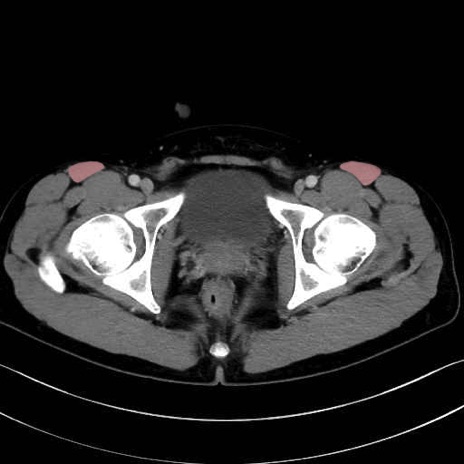

縫工筋 (Sartorius)